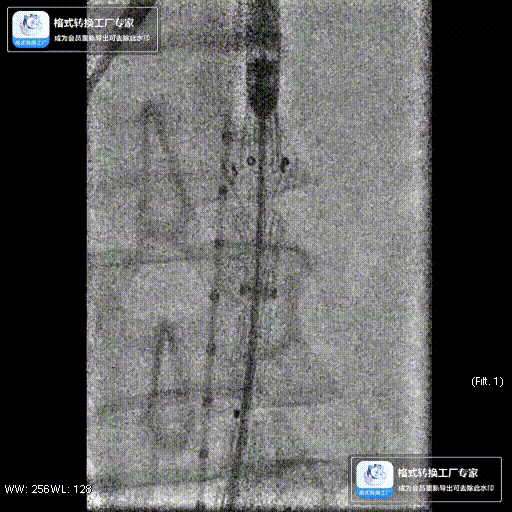

该技术主要适用于采用旋转式释放机制的支架。其核心操作步骤为:在主体支架释放出前2-3节后,轻微松开支架,然后反复反向旋转并上推输送鞘。 这一动作能促使已释放的近端支架段在瘤颈处产生可控的“堆叠”效应,从而更好地顺应瘤颈的弯曲形态,尤其是在大弯侧实现更紧密的贴壁,有效拓展了功能性密封区。

案例一(巨大成角瘤颈):患者瘤颈虽长但呈90度成角。在完成髂动脉重建后,采用Reverse技术释放主体支架。术中造影显示,支架完美贴合扭曲的血管大弯侧,术后一月复查CTA,原有的少量内漏已完全消失。